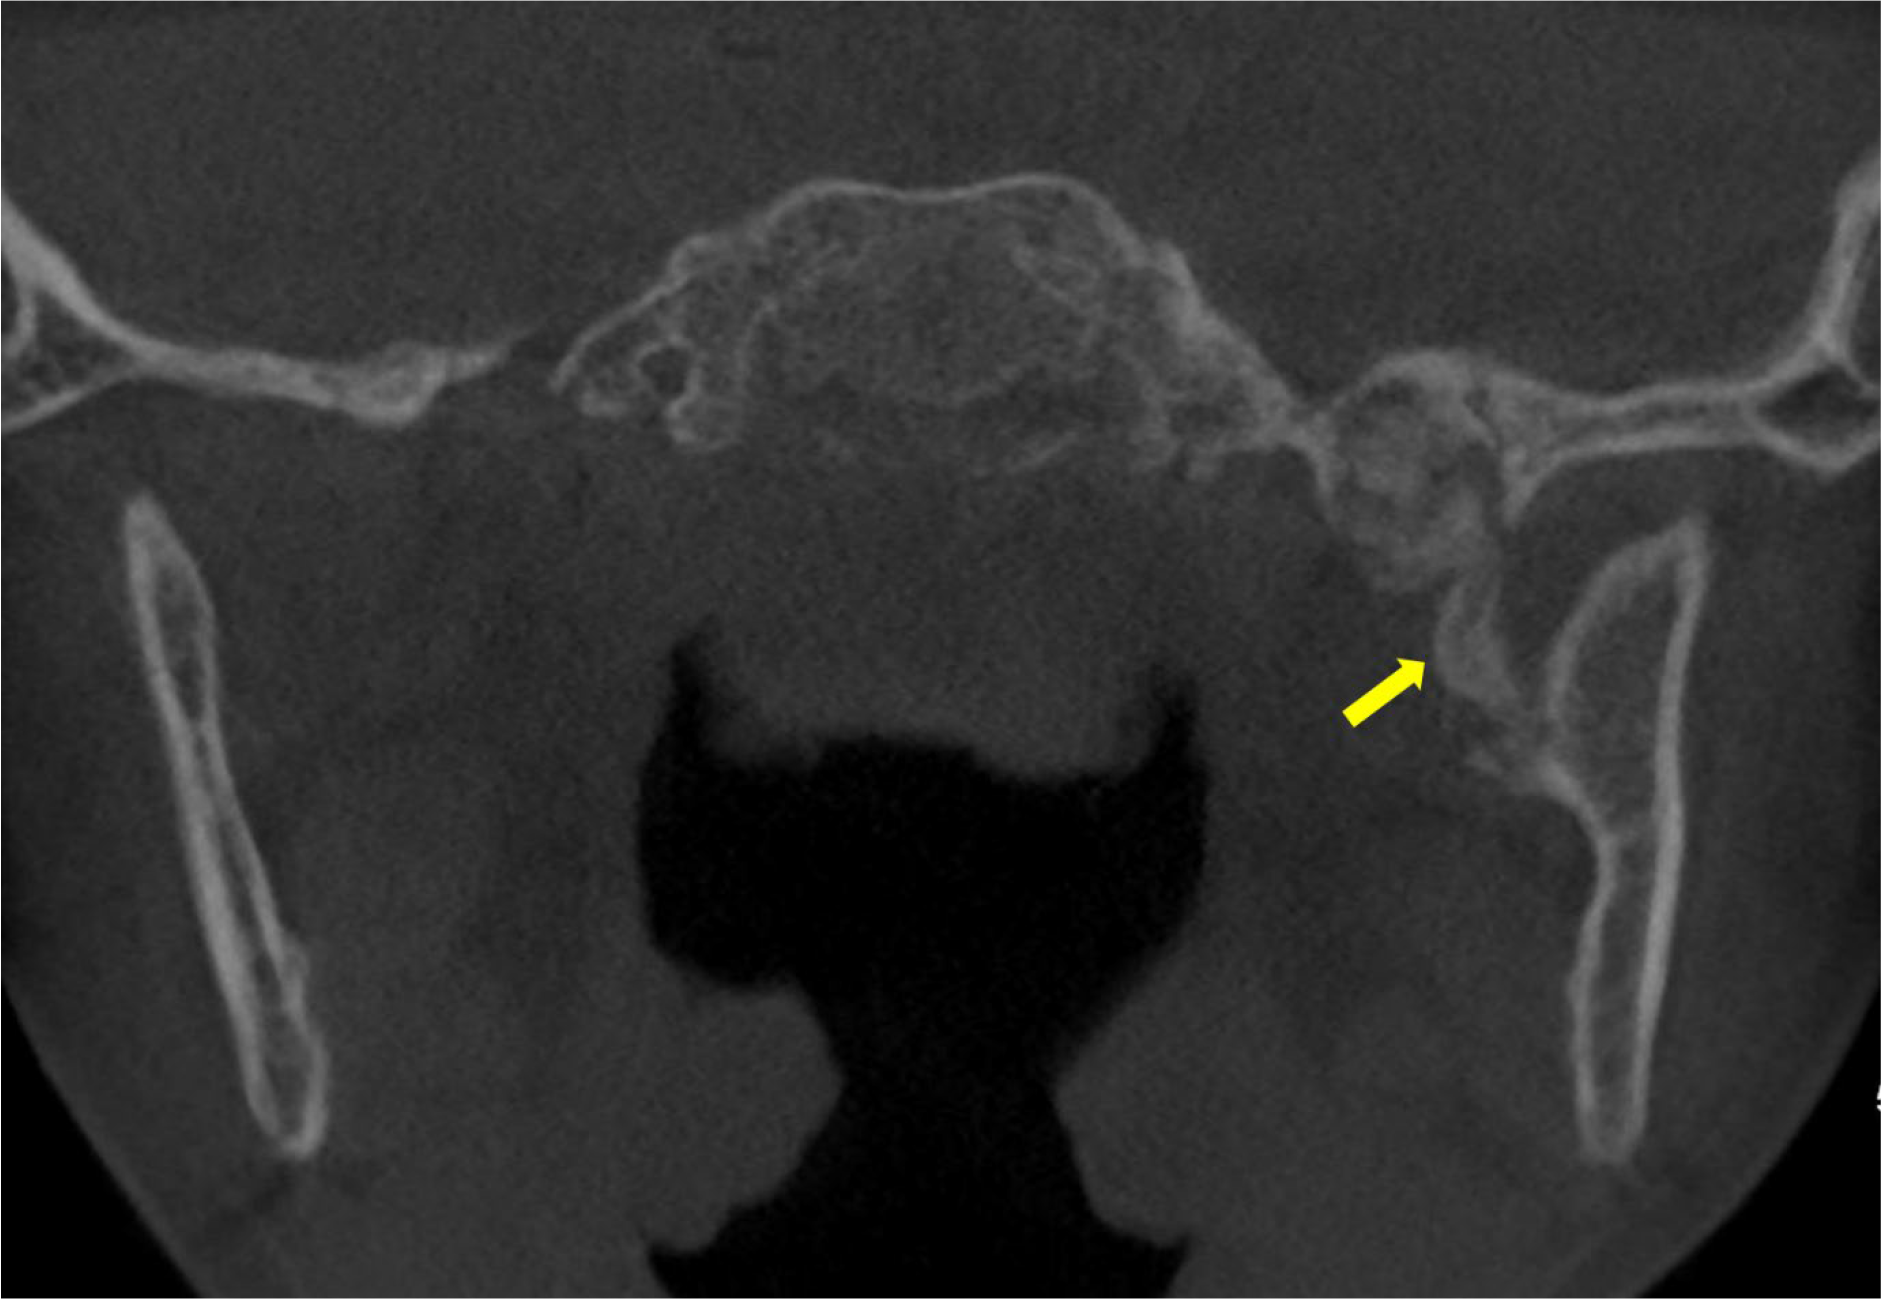

A computed tomography (CT) of the face revealed an oblique bony hypertrophy in the medial aspect of the left mandibular ramus (Figure 1). This multi‑fragmentary calcification connected the spine of the sphenoid bone and the Spix spine. It appeared to have a mass effect on the origin of the foramen ovale, with potential compression of the V3 nerve.

Figure 1

Unenhanced CT scan showing an ossified structure located between the left mandibular ramus and the spine the left sphenoid (arrow).